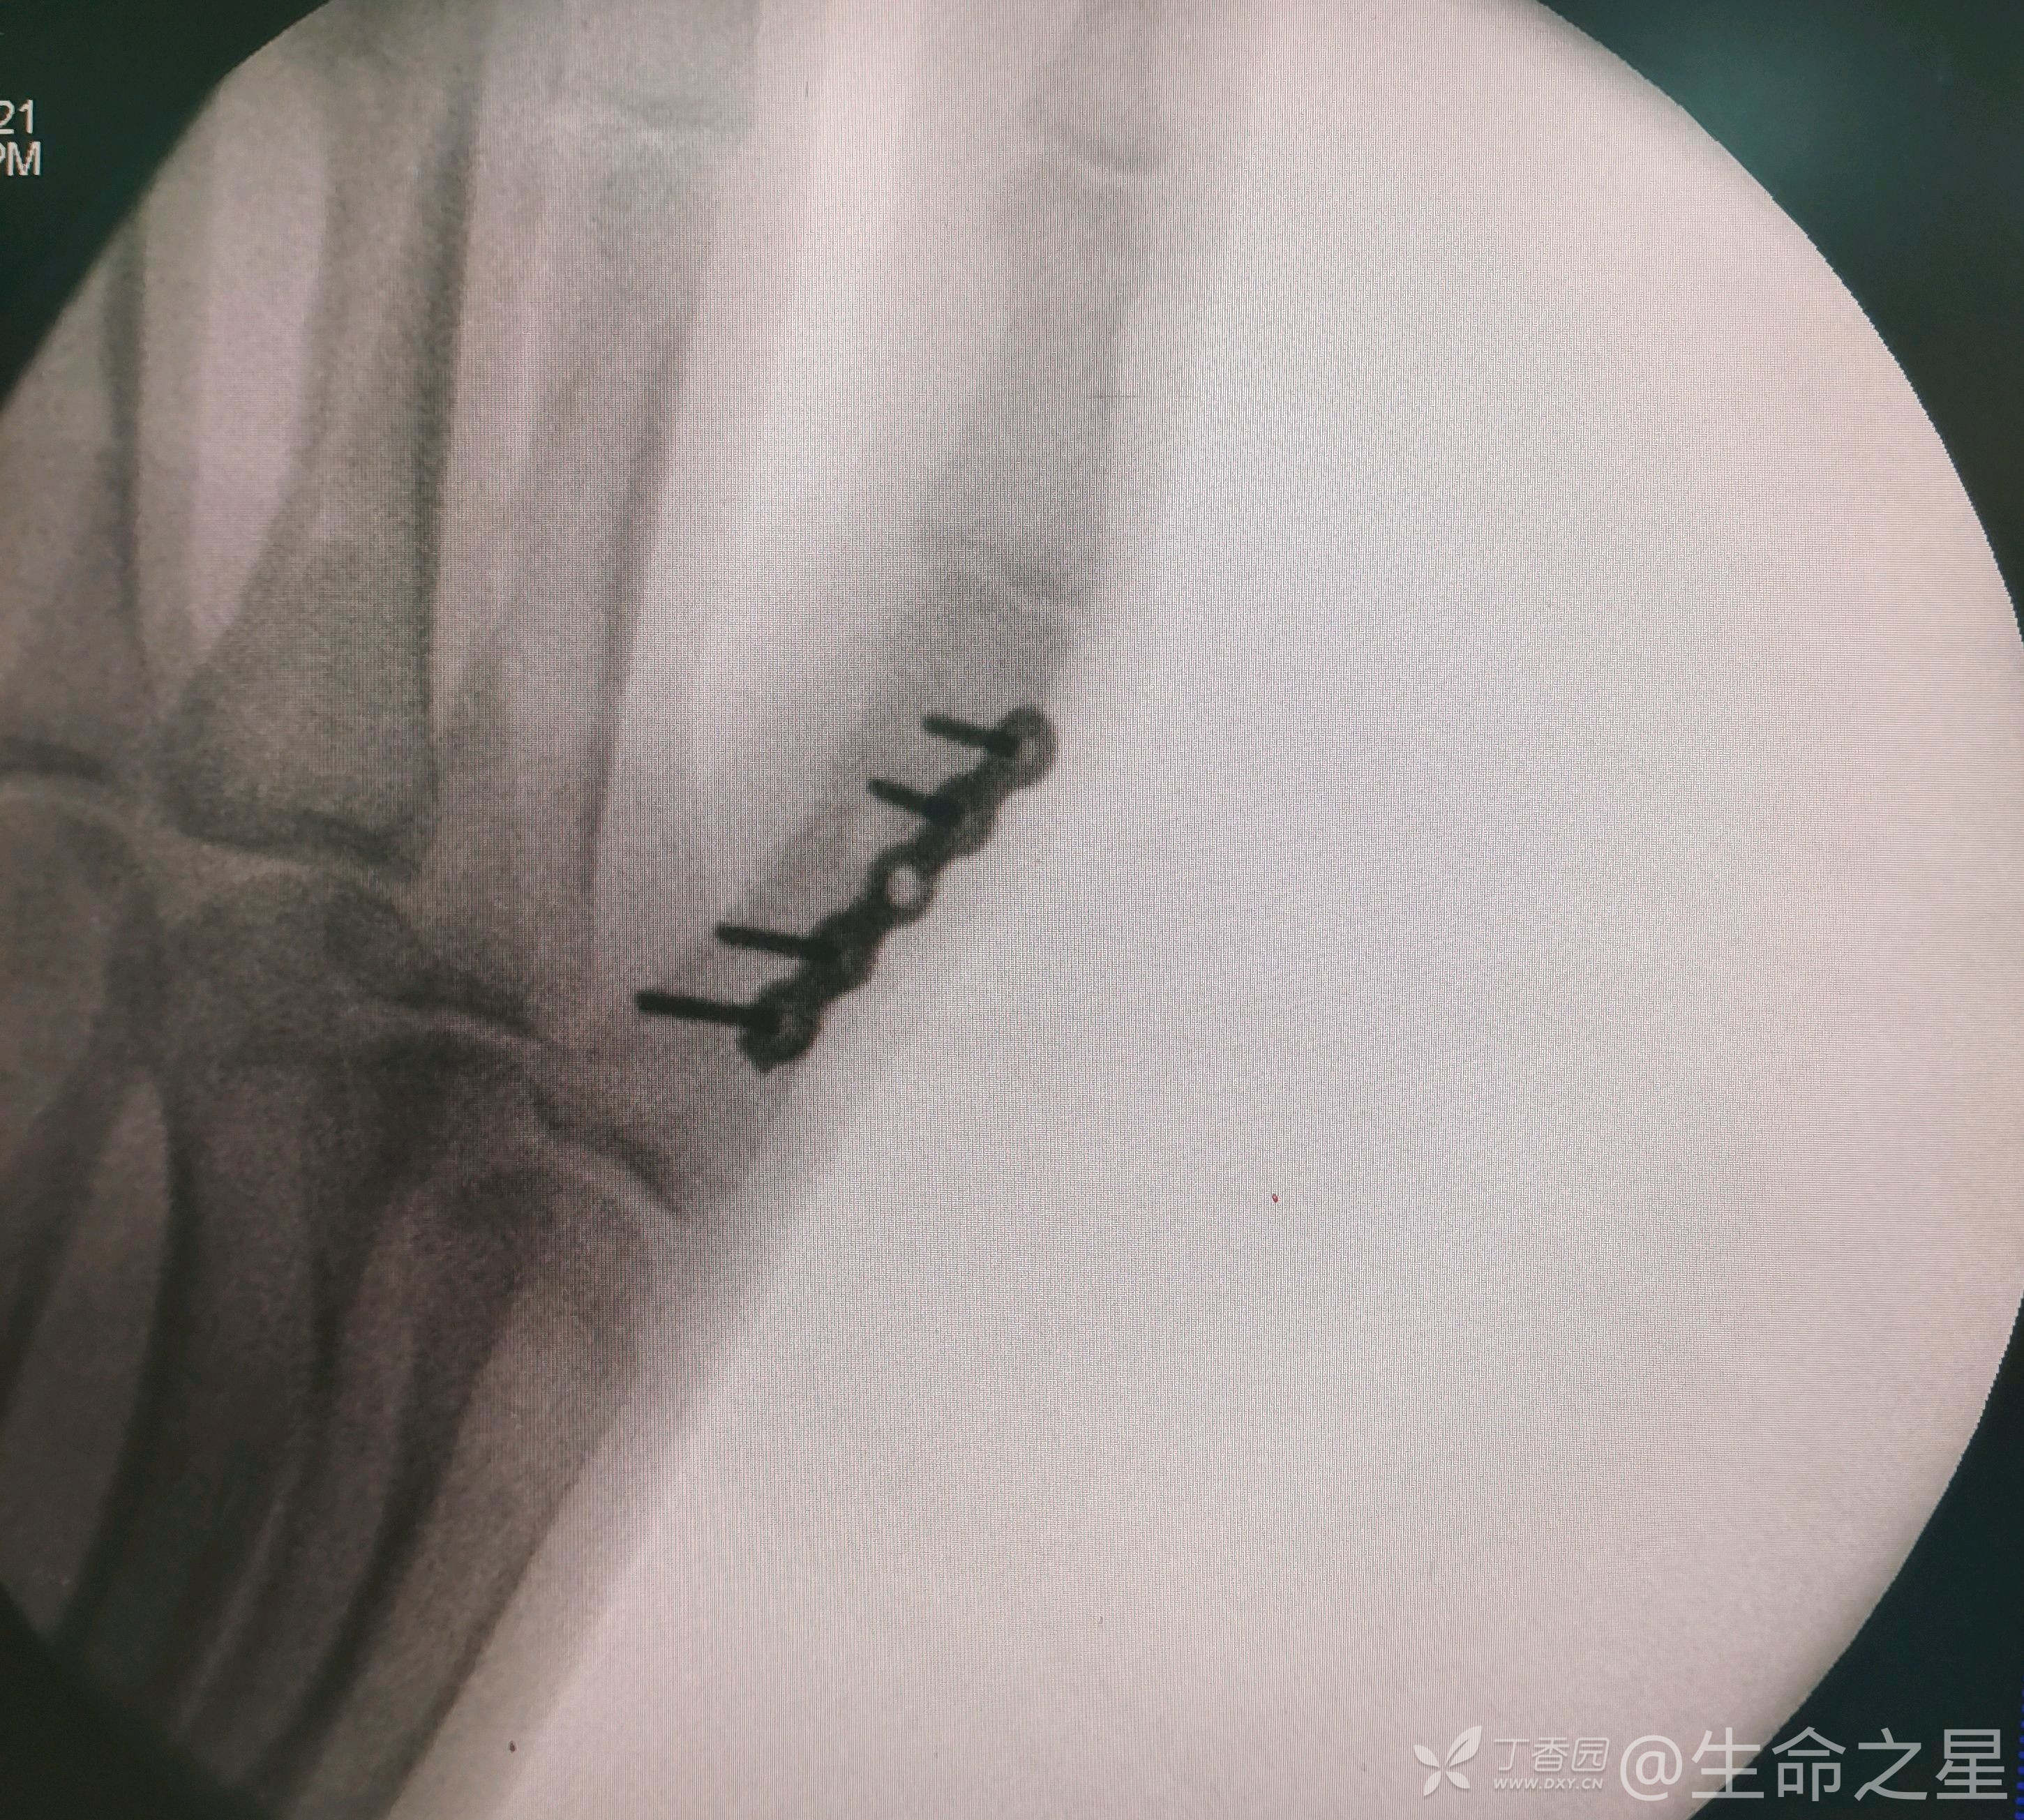

手术给予行切开复位内固定

手术耗时40分钟。

个人体会,手部及足部骨折,骨质小,操作难度大,要避免反复操作及返工,要一次到位,往往更考验技术

同一天做了股骨髁上和骶髂拉力螺钉,感觉做这手指时紧张出汗了😂